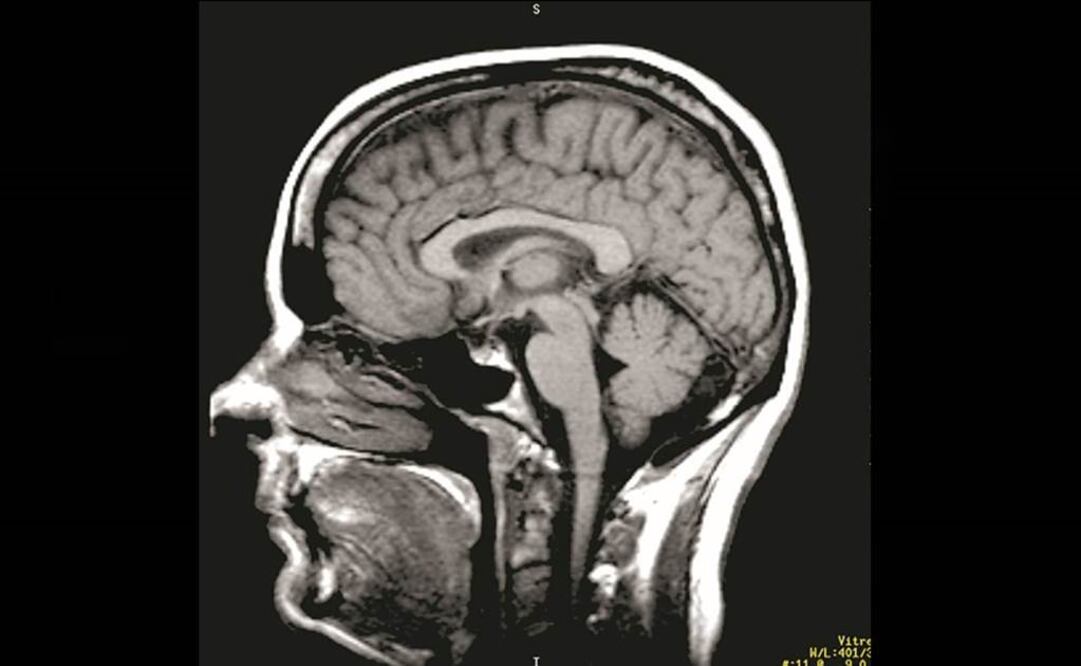

Un joven egresado de la licenciatura en Biomedicina de la Benemérita Universidad Autónoma de Puebla investiga en España el papel neuroprotector del factor de crecimiento insulínico tipo 1 (IGF-I) sérico en el cerebro modulado por el ejercicio.

Además, busca saber las estructuras del cerebro implicadas en estas diferencias: si el equilibrio del estado de ánimo se afecta con la entrada de IGF-I sérico al cerebro y si el mecanismo molecular implicado en la captura de IGF-I es diferente en hombres y mujeres.

Munive afirmó que existen evidencias de que el IGF-1 sérico entra al cerebro en condiciones fisiológicas, siendo el ejercicio físico uno de los estímulos más potentes para promover la captura de IGF-I por células cerebrales.

Según detalló, se ha reportado que IGF-I sérico en el cerebro media gran parte de efectos benéficos del ejercicio. “De manera interesante se ha visto que los efectos del ejercicio en deterioro cognitivo leve son sexualmente dimórficos”, indicó.